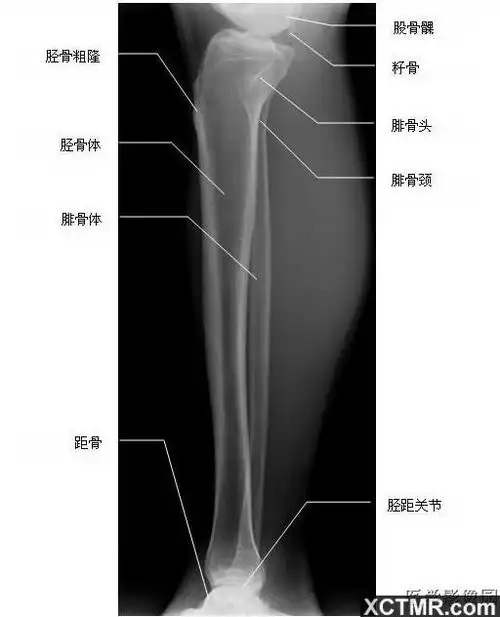

人体小腿骨解剖示意图-人体解剖图

胫腓骨侧位-x线-解剖图片